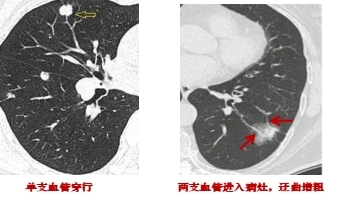

3.結(jié)節(jié)與血管的關(guān)系:如果肺結(jié)節(jié)內(nèi)部有血管匯入,周邊有血管伴行,且血管扭曲、增粗、變細或被中斷,往往提示惡性。